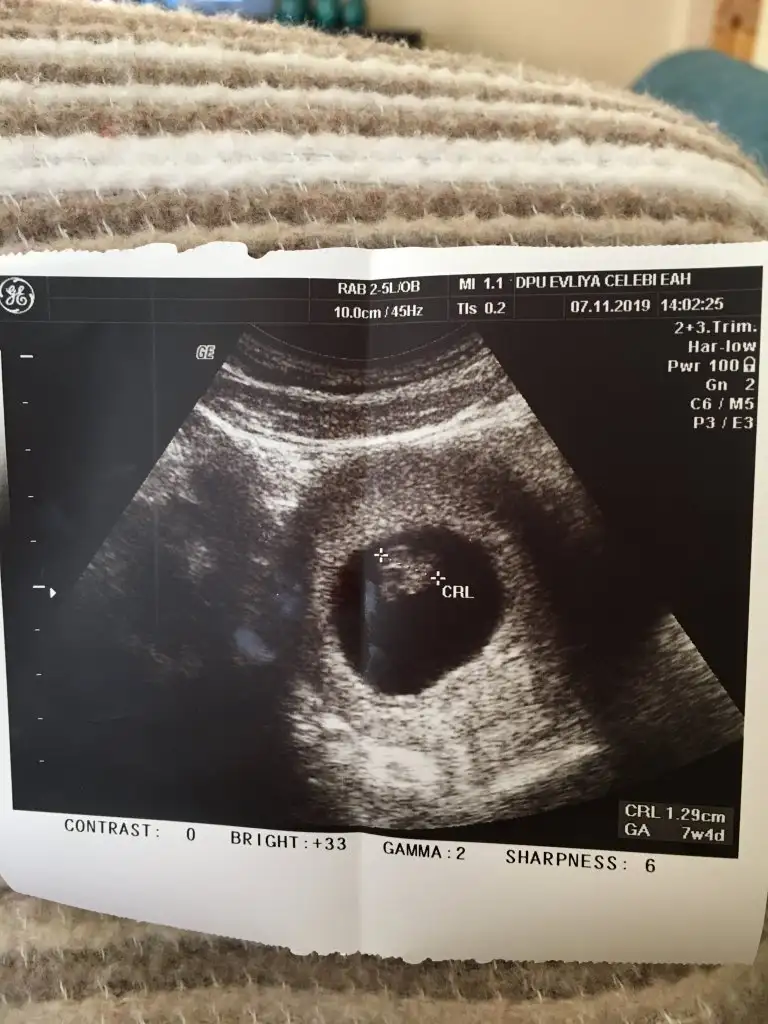

Canım senin bebişte 1.29 cmmişKızlarr bende baktım ultrason görüntüsünede ama bebeğin boyu kaç cm valla baktım baktım anlamadım8+1im ama ultrasona göre 2gün geriden geliyor demişti doktor tabi değişebilir bu durum demişti sağlıklı olsunda erken geç hiç önemli değil

Bebeğin boyu crl yazan :) 1.29 cm yaniKızlarr bende baktım ultrason görüntüsünede ama bebeğin boyu kaç cm valla baktım baktım anlamadım8+1im ama ultrasona göre 2gün geriden geliyor demişti doktor tabi değişebilir bu durum demişti sağlıklı olsunda erken geç hiç önemli değil

Canim 1.29 cmKızlarr bende baktım ultrason görüntüsünede ama bebeğin boyu kaç cm valla baktım baktım anlamadım8+1im ama ultrasona göre 2gün geriden geliyor demişti doktor tabi değişebilir bu durum demişti sağlıklı olsunda erken geç hiç önemli değil